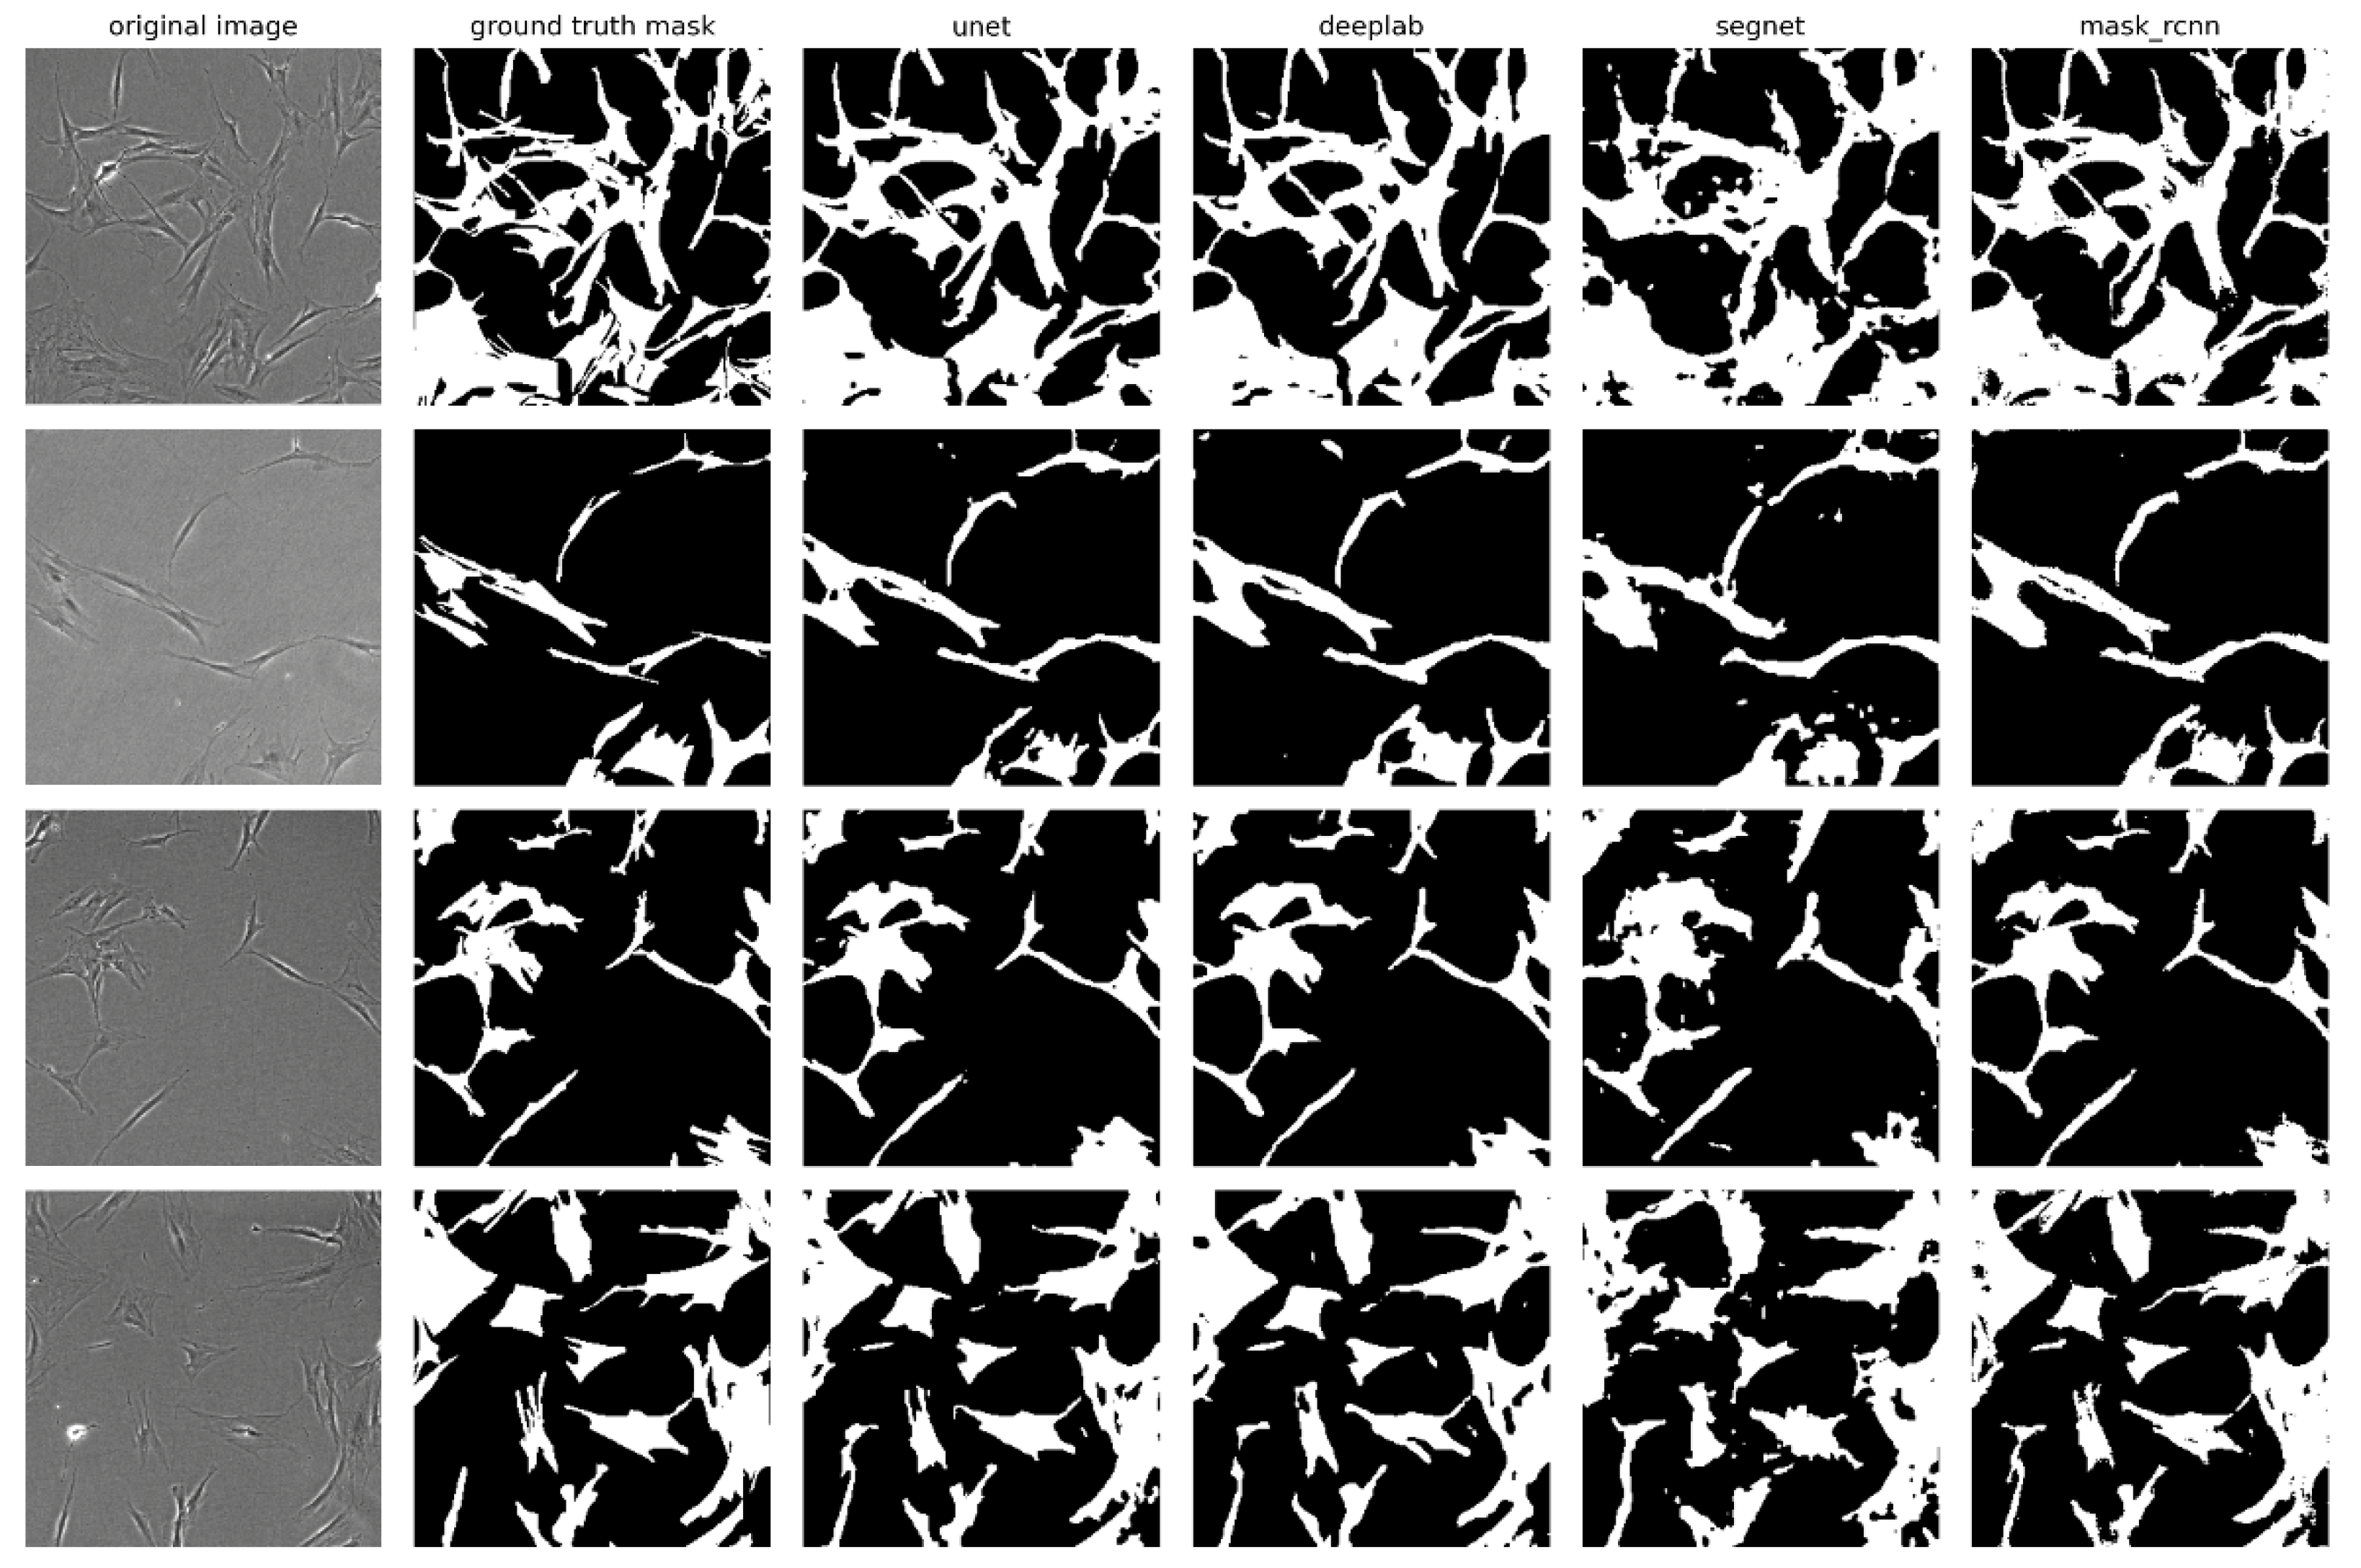

2.3. Visual Evaluation of Segmentation Performance

For a visual evaluation of the performance of the investigated neural network models, several examples of original micrographs from the validation sample, along with ground truth masks and predicted masks, are presented in Figure 4, which illustrates a comparison between actual and predicted segmentations. The U-Net, DeepLabV3+, and Mask R-CNN models demonstrated the highest accuracy in extracting cell boundaries, particularly when compared to the SegNet model, which performed less effectively in extracting complex and small structures of cell morphology. On the masks predicted by SegNet, flaws in segmentation such as rough boundaries and missing details can be observed, especially in areas where cells have curved or complex shapes. Despite the high segmentation accuracy of the Mask R-CNN model, the masks predicted by this model are characterized by poorly defined cell edges. These irregularities appear as jagged contours. This may be due to the fact that Mask R-CNN, focusing on the instance-segmentation task, selects objects of certain classes in the image. The algorithm focuses on the exact localization of objects but does not always reproduce boundaries. In this respect, U-Net and DeepLabV3+ demonstrate greater accuracy in contour reconstruction.

Figure 4. Examples of segmentation of MSC micrographs by neural network models: original images, ground truth masks, and masks predicted by U-Net, DeepLabV3+, SegNet, and Mask R-CNN models. The micrographs were captured at a magnification of 40×.